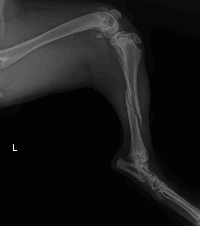

Após exames recebemos a seguinte notícia:

Em relação às fraturas, além da perninha esquerda, ela tem também fraturas em pelve. O ortopedista nos repassou o orçamento de R$2950,00 para o procedimento cirúrgico (incluindo o valor da anestesia e uma diária de pós operatório). Na ultrassonografia abdominal, foi identificado apenas sinais de gastrite. Os exames de sangue devem ser liberados agora pela manhã ainda.